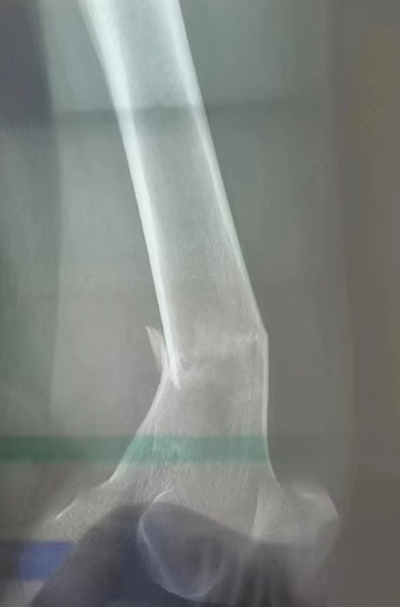

疫情就是命令,防控就是責任,生命重于泰山!對于這樣一位特殊患者,骨中心確定了由創傷骨科張學東主任醫師和胡國東副主任醫師為核心的治療小組。而對于有20多年臨床工作經驗的兩位術者來說,身穿防護服、佩戴防護面屏,外加N95口罩,這樣“高規格裝備”的手術還是第一次。經過前期緊鑼密鼓的準備,李女士很快經專門通道被送到了應急負壓手術室。這是一個沒有硝煙的戰場,無影燈下,所有人都有條不紊地忙碌著……麻醉醫師李明哲、趙賢姬密切監測患者生命體征,巡回護士邢燦、陳儷文與器械護士劉佳蘊全神貫注地配合著手術,所有人都穿著防護服,為這臺特殊手術爭分奪秒、保駕護航……一個半小時的手術,悶熱感絲毫沒有讓大家有任何的松懈,當脫下厚厚的隔離設備,汗水已經浸透了手術衣。術后,李女士再次經專門通道送回到感染科病房,回病房后立即啟動快速康復流程。5月3日下午,李女士病情穩定,復查骨折手術X線片顯示骨折復位滿意,請示指揮部指示后即可出院。